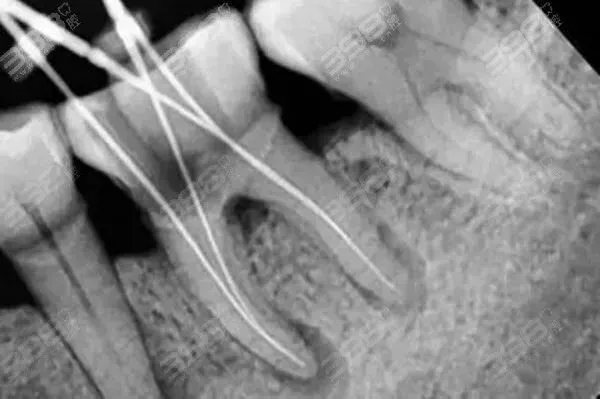

显微根管治疗就是使用了一种更加数字化的仪器,也就是显微镜,提供充足的光源进入根管,并将根管系统放大,使医生能够清晰地看到根管内部的结构,从而进行更准的治疗。根管治疗的原理是通过物理和化学的方法,将感染的牙髓组织从牙髓和根管系统中清除出去,并进行根管的消毒和充填,以防止再感染。